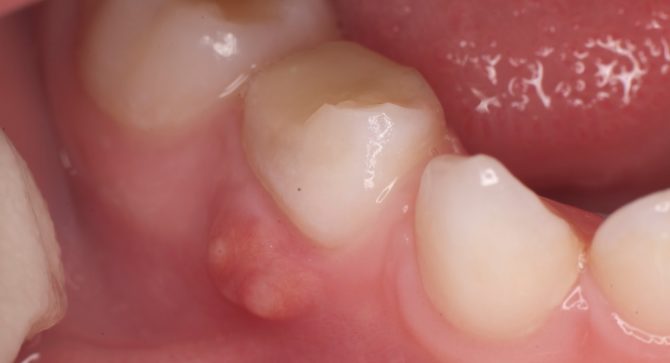

Фото: так выглядит десна с нарывом

Гной на десне появляется над зубом или между зубом и десной в зависимости от локализации инфекции. Дальнейшее формирование гнойника можно распознать по следующим признакам:

У взрослого и ребенка признаки абсцесса идентичны, гной в десне выглядит как на фото.